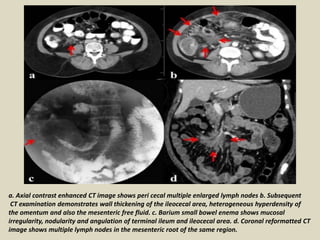

a. Axial contrast enhanced CT image shows peri cecal multiple enlarged lymph nodes b. Subsequent

CT examination demonstrates wall thickening of the ileocecal area, heterogeneous hyperdensity of

the omentum and also the mesenteric free fluid. c. Barium small bowel enema shows mucosal

irregularity, nodularity and angulation of terminal ileum and ileocecal area. d. Coronal reformatted CT

image shows multiple lymph nodes in the mesenteric root of the same region.